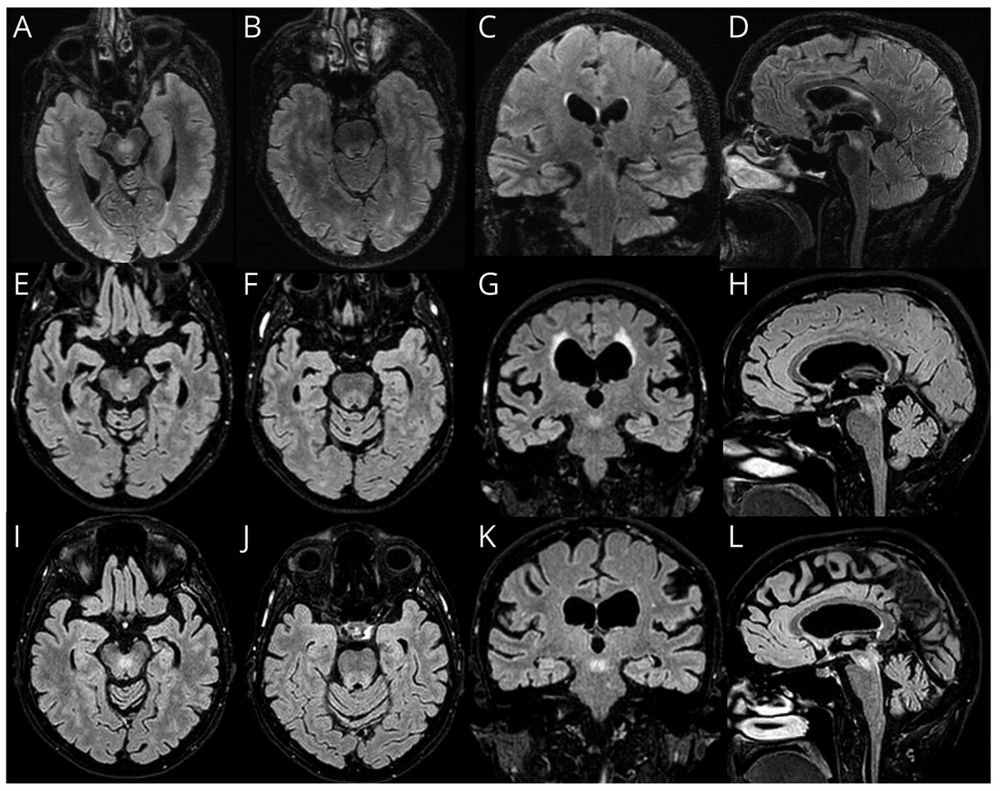

The superior cerebellar peduncle has been *the* imaging clue for POLR3A-related late-onset spastic ataxia. It has now been reported in 60% of a cohort of 87 patients with GAA-FGF14 ataxia (SCA27B), independent of disease duration or GAA size (≤300 vs >300).

Neuroradiological findings in GAA-FGF14 ataxia (SCA27B): more than cerebellar atrophy. https://www.medrxiv.org/content/10.1101/2024.02.16.24302945v1

Background and Objectives GAA-FGF14 ataxia (SCA27B) is a recently reported late-onset cerebellar ata